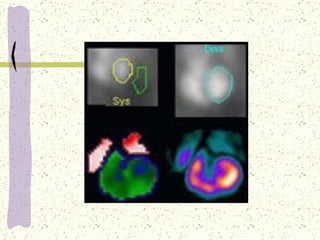

ECOCARDIOGRAFIA